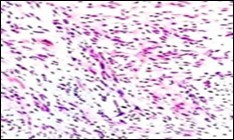

Figure 9.Soft tissue perineurioma with plentiful collagenous fibrils intermixed with lamellar neural tissue with elongated cytoplasmic extensions and wavy, pointed nuclei 18.